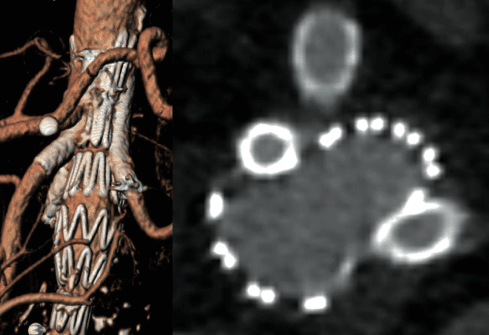

>>> Du risque de rupture qui est fonction des trois facteurs indépendants suivants : le plus grand diamètre, la poursuite de l’intoxication tabagique et une insuffisance respiratoire. Interviennent également dans la décision, car associés à un plus grand risque de rupture, la notion d’antécédents d’anévrysme, voire de rupture dans la famille ; le sexe féminin ; l’aspect sacciforme plutôt que fusiforme ; et une croissance rapide (> 0,5 cm par an). La figure 1 montre le pourcentage de survenues de rupture en fonction du temps rapporté au diamètre initial. Les figures 2 et 3 illustrent les aspects respectivement fusiforme et sacciforme d’AAA en examen tomodensitométrique.